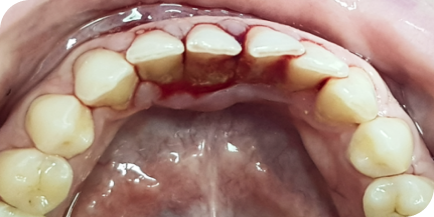

Случай из практики.

Лечение пародонтита

Пациентка (Ольга, 38 лет) обратилась в нашу клинику с жалобами на боль в дёснах, подвижность зубов, неприятный запах изо рта.

Мы провели полную диагностику. Диагноз — хронический генерализованный пародонтит средней степени тяжести. Выявлены проблемы: подвижность зубов 1-й степени, пародонтальные карманы более 5 мм, убыль костной ткани на 1/2 длины корня зуба.

Пародонтит — это воспалительные поражение окружающих тканей зуба, проникающее глубоко под десну. Воспаление вызывает разрушение костной ткани и связок зуба. На исходном фото это хорошо видно.

Исходное состояние